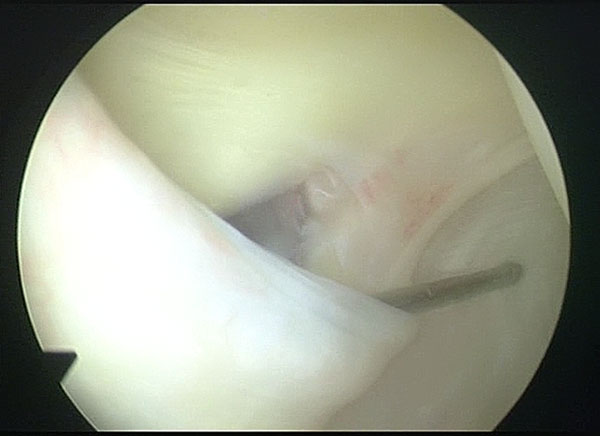

Arthroscopic Management of Baker's CYST